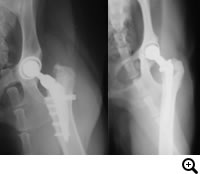

THR(Total Hip Replacement)/ 股関節全置換術

Micro THR(Micro Total Hip Replacement)/ 小型犬・猫用股関節全置換術

全股関節置換術は股関節形成不全やその他の股関節の異常(レッグペルテス、骨頭骨折等)に対して行われる根治的治療法で、機能の回復に関しては現在のところ最もすぐれた治療法です。機能しない、あるいは痛みを持つ股関節をチタンの人工関節に取り替える方法です。6カ月齢からあらゆる年齢で可能な手術です。

DPO(Double Pelvic Osteotomy)/ 二点骨盤骨切り術

TPO(Triple Pelvic Osteotomy)/ 三点骨盤骨切り術

5カ月齢~8カ月齢までの症例で有効な手術。腸骨・恥骨の二点もしくは腸骨・恥骨・坐骨の三点に骨切りをおこない、寛骨臼による大腿骨頭のカバーがよくなるよう腸骨を外側へ回転させる術式です